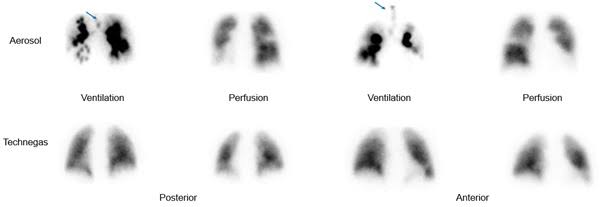

Ventilation perfusion lung scan (વેન્ટિલેશન પરફ્યુઝન લંગ સ્કેન):

- વેન્ટિલેશન પરફ્યુઝન લંગ સ્કેન એ ન્યુક્લિયર મેડીસિન ટેસ્ટ છે જેની મદદથી લંગના એર ફલો અને બ્લડ ફલોને ઇવાલ્યુટ કરવામાં આવે છે.

- જેમાં રેડિયોએક્ટિવ સબટન્સને ઇન્હાલ કરવામાં આવે છે અને તેની મદદથી એર ફલો જાણવામાં આવે છે. તેવીજ રીતે ઇન્ટ્રાવેન્સ્લી રેડિયોએક્ટિવ સબટન્સ એડમિન્સ્ટર કરવામાં આવે છે જેથી બ્લડ ફલો જાણી શકાય.